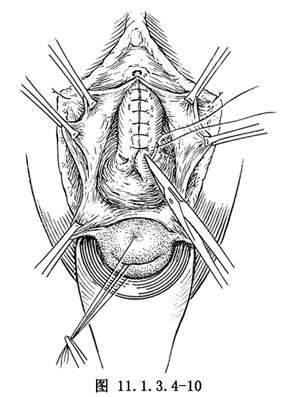

(4)從尿道內口兩側開始,以4號絲線或2-0鉻制腸線褥狀縫合恥骨-膀胱-宮頸筋膜(圖11.1.3.4-10)。打結後抽動導尿管,有收縮感爲縫合鬆緊適度。